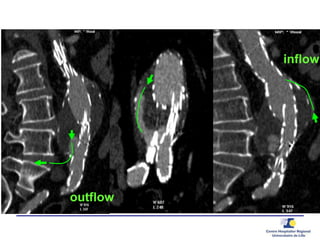

Inflow and Outflow

Inflow? Outflow?

outflow

inflow